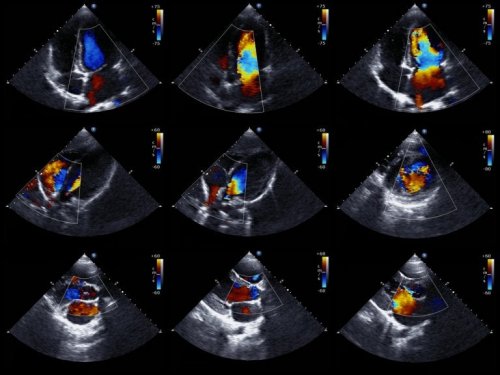

I medici sono in grado di diagnosticare questa anomalia già prima della nascita. A tal proposito, si avvalgono dell’ecocardiogramma fetale. Questa tecnica utilizza le onde sonore per creare un’immagine del cuore in movimento.

Grazie a ciò, è possibile esaminare l’aspetto del cuore e valutarne il funzionamento quando il bambino è ancora nell’utero. Con le informazioni ottenute, i medici sono in grado di programmare il trattamento del nascituro.